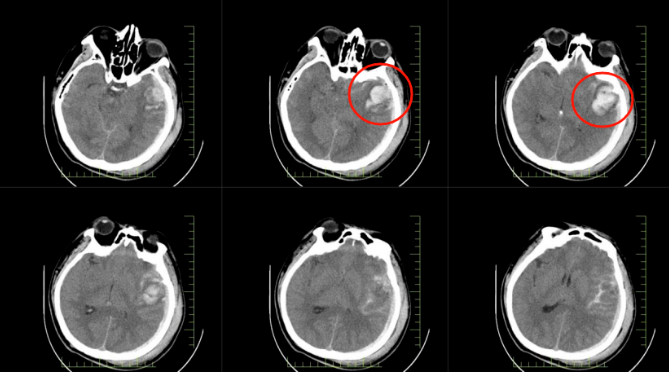

患者郭先生因高處墜落,送達(dá)醫(yī)院時(shí)已陷入昏迷。經(jīng)急診全面檢查,被確診為顱腦損傷重型、腦挫裂傷伴腦內(nèi)血腫、創(chuàng)傷性蛛網(wǎng)膜下腔出血等多項(xiàng)嚴(yán)重病癥。顱內(nèi)出血、顱壓驟升,每一項(xiàng)診斷都如同高懸的達(dá)摩克利斯之劍,威脅著患者的生命。

*患者顱內(nèi)出血影像圖

術(shù)中探查患者顱內(nèi)出血量極大,腦組織水腫嚴(yán)重,受壓明顯。在神經(jīng)外科張友軍主任的帶領(lǐng)下,手術(shù)團(tuán)隊(duì)?wèi){借精湛的醫(yī)術(shù)和豐富的經(jīng)驗(yàn),爭(zhēng)分奪秒地進(jìn)行止血操作,降低顱內(nèi)壓。經(jīng)過(guò)長(zhǎng)達(dá) 4 小時(shí)的艱苦奮戰(zhàn),手術(shù)成功完成,患者隨即轉(zhuǎn)入重癥醫(yī)學(xué)科接受進(jìn)一步監(jiān)護(hù)。

*患者顱內(nèi)術(shù)后影像圖